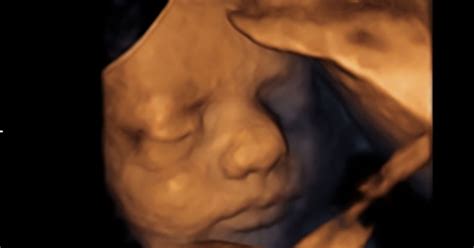

Mnoge ženske takoj po zaužitju prve tablete svojo odločitev obžalujejo, vendar jih večina ni seznanjena z režimom »razveljavitve« teh tablet, ki lahko - če se izvede pravočasno - reši življenje njihovega otroka. V navodilih teh tablet so navedeni nevtralni izrazi, ki zabrišejo kruto realnost. Ženskam ni nazorno povedano o močnih krvavitvah in bolečih krčih, ki jih mnoge doživijo po zaužitju. Uporabljeni nevtralni izrazi se spretno izognejo realnemu poimenovanju, ženske pa ne pripravijo na to, da bo plod v 10. tednu nosečnosti že povsem razvit. Mnoge ženske so iskreno spregovorile o tem, kako je dejansko potekal ta boleč proces, ko so se povsem same znašle v izjemno težki situaciji, ko so v straniščni školjki ali na preprogi v kopalnici zagledale svojega otroka. Celoten proces so doživele kot travmo.